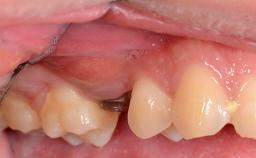

The patient presented with a failing tooth-supported fixed dental prosthesis with cantilever extension replacing the right maxillary central incisor. His chief presenting complaint was poor esthetics, in particular the dark discolored margin around the abutment tooth, the maxillary left central incisor. He reported a history of trauma at a young age, which necessitated the replacement of his maxillary right central incisor as well as root canal therapy of the adjacent left central incisor. The existing prosthesis had been in situ for over 20 years. The initial periapical radiograph displayed good proximal bone levels at the adjacent teeth and a wide incisive canal, which was a concern. The left central incisor presented a very wide root canal treatment with compromised radicular dentin thickness, which was a consideration in the decision between a new tooth-supported fixed dental prosthesis vs. an implant-supported prosthesis. After a lengthy discussion on the risks and benefits of both treatment options, the patient decided on a single-tooth implant replacement.

Soft Tissue Anatomy Intact Defective

Bone Volume Horizontally and vertically sufficient Horizontally deficient Deficient vertically or deficient vertically AND horizontally